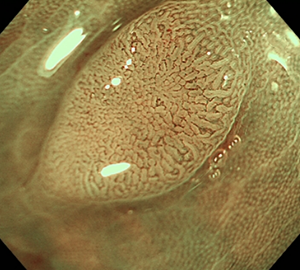

コールドスネアポリペクトミー(CSP)

合併症の非常に少ない優れた治療法であることから、近年大腸ポリープの外来切除法として急速に施行件数が増えてきています。当院ではこのコールドスネアポリペクトミーを主体としたポリープ切除を行っています。

| 1:ポリープを見つけます。 | 2:狭帯域光画像併用拡大観察で詳細に観察します。 | |

| 3:病変をスネアに通します。 | 4:周囲の正常粘膜をしっかり入れながら、病変を絞扼していき... | |

| 5:切除します。切除検体は吸引回収し病理検査を行います。 | 6:切除後に洗浄・観察して、病変の遺残ががないことを確認します。 |